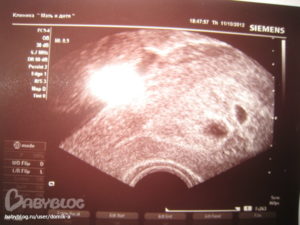

Нормальными показателями размеров зародыша принято считать:

- Внутренний диаметр плода равен 18–22 мм.

- Копчико-теменной размер зародыша достигает 3–6 мм. Данные актуальны на 28 день после подсаживания клетки.

- Желточный мешочек должен равняться 3 мм в диаметре.

Сведения не дают на 100% корректную картину, поскольку зависят от дня имплантации эмбриона. Обычно для наступления беременности необходимо 3–10 дней, в зависимости от подготовки среды в матке на день переноса зародышей. Сроки внедрения эмбрионов в матку еще зависят от дня продолжительности жизни бластоцисты. Обычно пятидневки быстрее имплантируют, чем трехдневки.